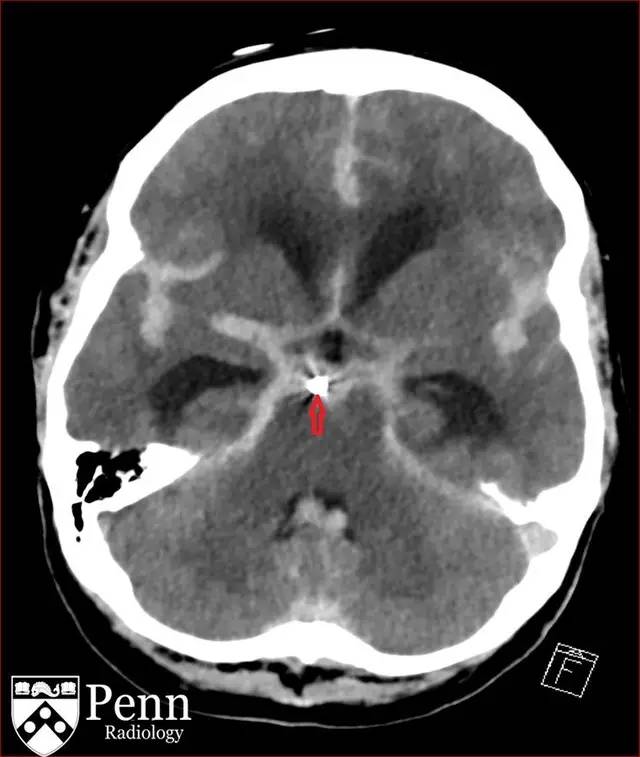

图 9 动脉瘤栓塞术后 CT,可见高密度的线圈影(红色箭头)

使用单个 1.5 x 2 cm 的纳米线圈对动脉瘤进行栓塞后随访 CT。